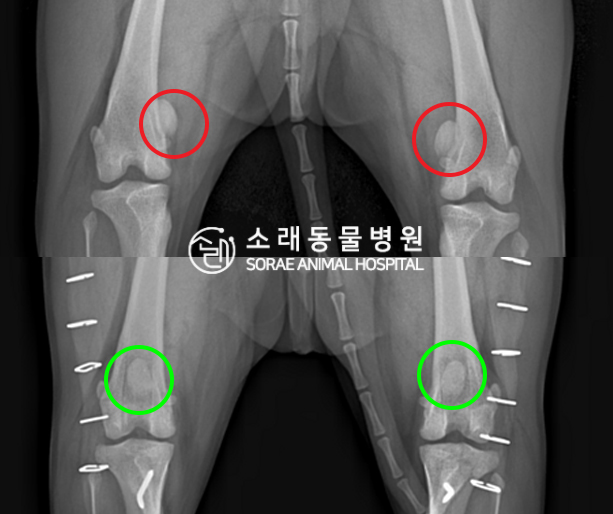

수술전과 수술후에 촬영한 솜이의 슬개골

방사선 사진입니다. 나란히 놓고 비교해보니

슬개골의 위치에 확연한 차이가 있는 것을

확인해 볼 수 있는데요. 내측으로 탈구되어 있던

슬개골이 원래 제자리인 활차구에 예쁘게

자리 잡고 있는 모습을 확인할 수 있었습니다.